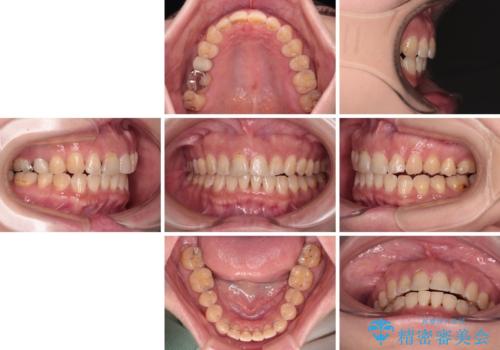

- 飛び出た上の前歯を気にして来院された患者様です。

奥歯の咬み合わせは、上顎歯列が理想的な一よりも数mm前方にある状態でした。

舌の突出癖が原因で上下の歯に大きなスペースが生じていたため、舌のトレーニングをしっかり行っていただくことで、上顎歯列をスムーズに移動させることができました。